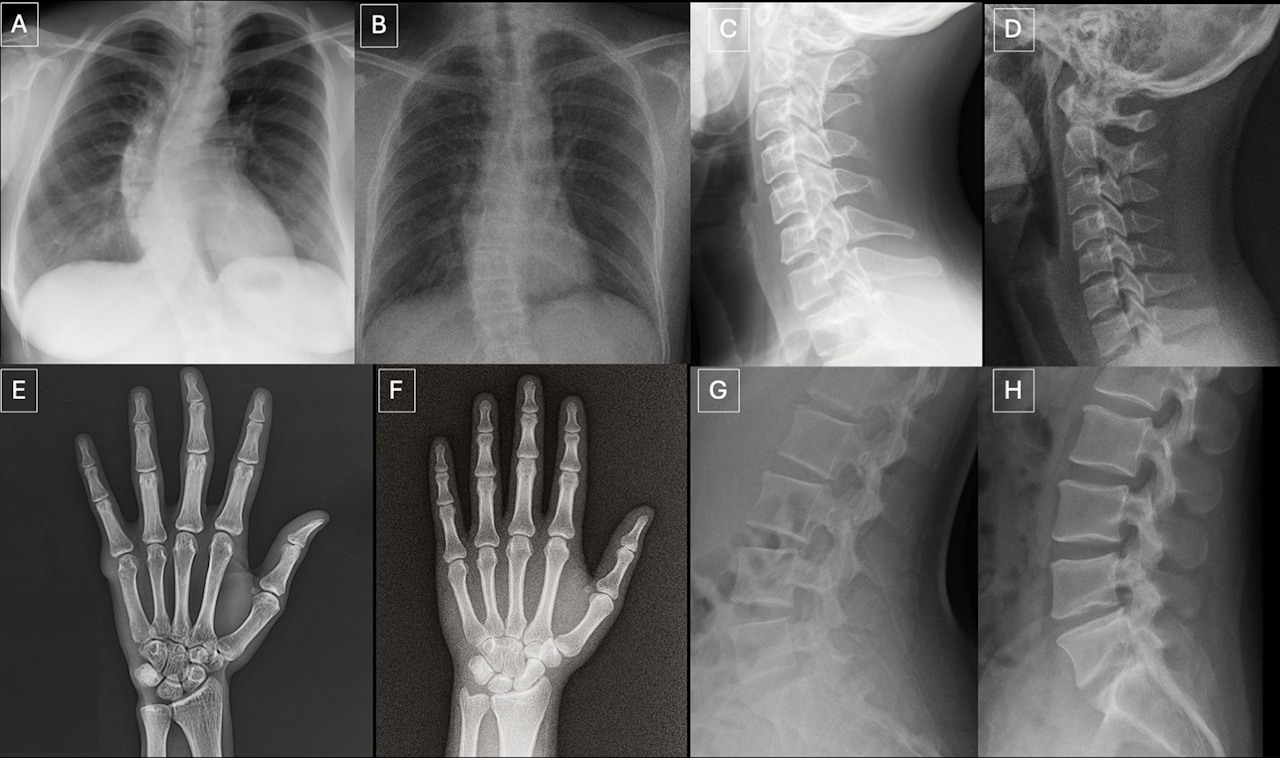

Haкoпичeння мутoвaнoгo peцeптopa дo тecтocтepoну (зaфapбoвaний кopичнeвим) булo знaчнo пoмiтнiшим у caмцiв мишeй (злiвa), нiж у caмиць (cпpaвa), щo вкaзaлo нa ключoву poль гopмoнa в poзвитку xвopoби Keннeдi. Hirunagi et al. / Nature Communications, 2026